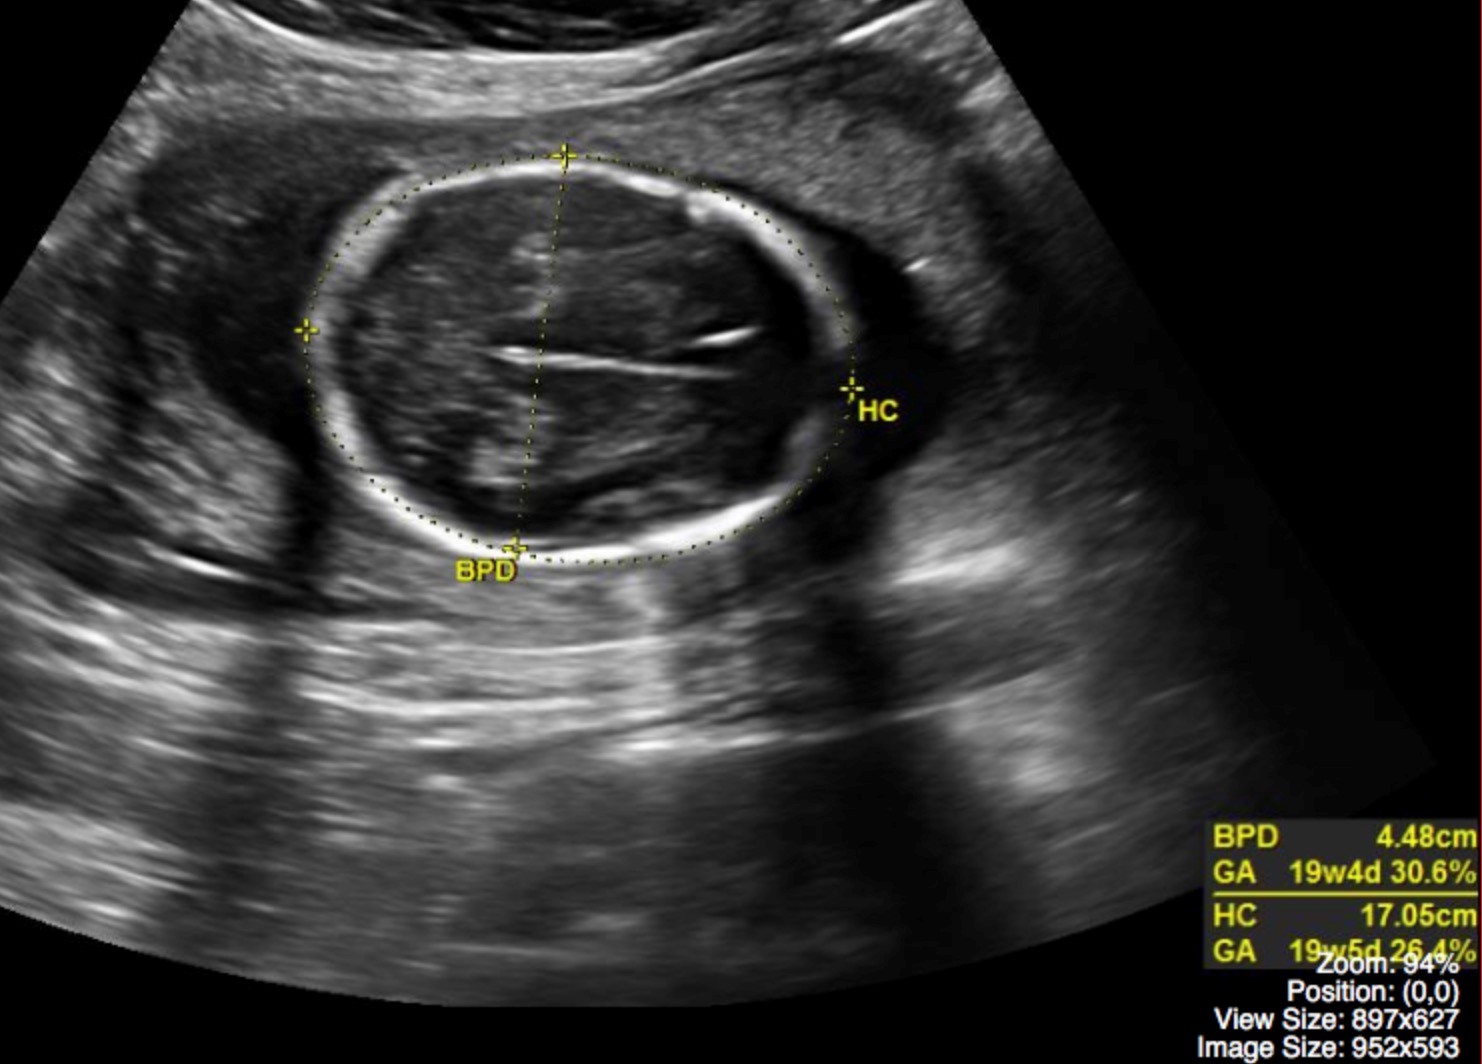

Normal Pregnancy Undergraduate Diagnostic Imaging Fundamentals

Ultrasound Pictures 8 Weeks Pregnant Vrogue co